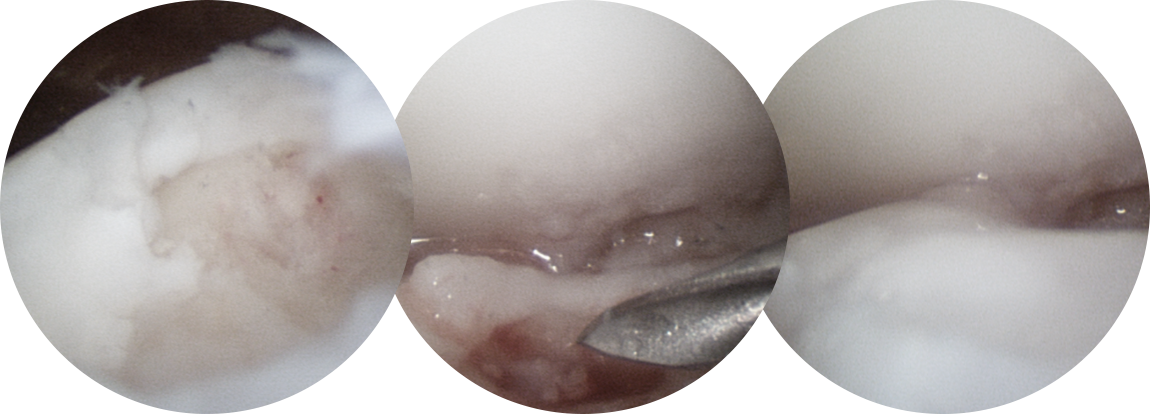

관절경을 통하여 손상된 연골 부위를 정리하고 뼈에 작은 구멍을

여러 개 뚫어서 연골 재생을 유도하는 방법입니다.

섬유성 연골로 재생되나 미세 천공술 단독으로도

특히 발목에는 효과가 좋습니다.

연골 손상이 있는 부위에 작은 구멍을 여러 개 내준 후, 골수에서부터 좋은 피가 잘 올라오는 것을 확인합니다.

연골 재생술을 같이 하는 것이 계획되었다면 콜라겐 혹은 줄기 세포로 결손부위를 도포해줍니다.

* 환자에게 받은 소중한 자료입니다.

거골의 내측부 연골 병변에 대해서 관절경을 통해 미세천공술과 콜라겐 주입술을 시행하였으며,

수술 5개월째 결손 부위에 연골이 잘 생성되어 있는 소견이 관찰되었습니다.